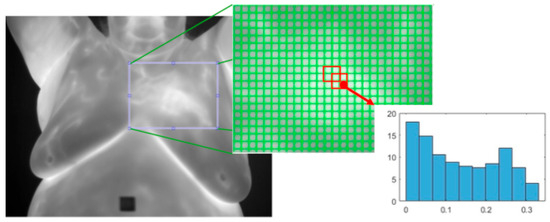

- Histogram of Oriented Gradients (HOG): This [33] is a texture feature extractor that is also applied to the detection of objects in images. An image is split into non-overlapping cells of a predefined size. Regions are defined as a fixed number of cells and may overlap. The gradient is calculated for each pixel and the histogram of all the gradients within each cell is calculated. All the cell histograms of gradients within a region are normalized and concatenated into a single vector and then all the region vectors are concatenated into one vector. See Figure 11.